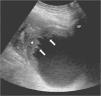

Radiología Pseudotumor inflamatorio de la vejiga urinaria

Pseudotumor inflamatorio de la vejiga urinaria

Inflammatory pseudotumor of the urinary bladder